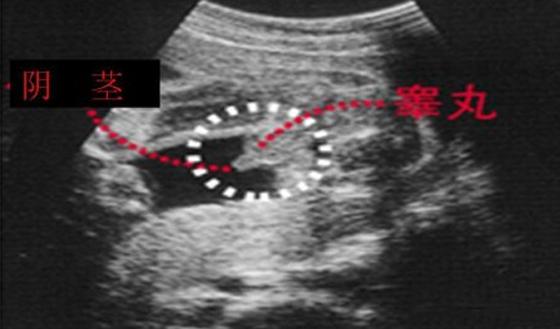

四維彩超,不管是看胎兒在腹中的發(fā)育情況,還是看胎兒性別,都讓人深信不疑。那么,四維彩超上面真的有男女暗示嗎?四維彩超又是怎么看男女的呢?...